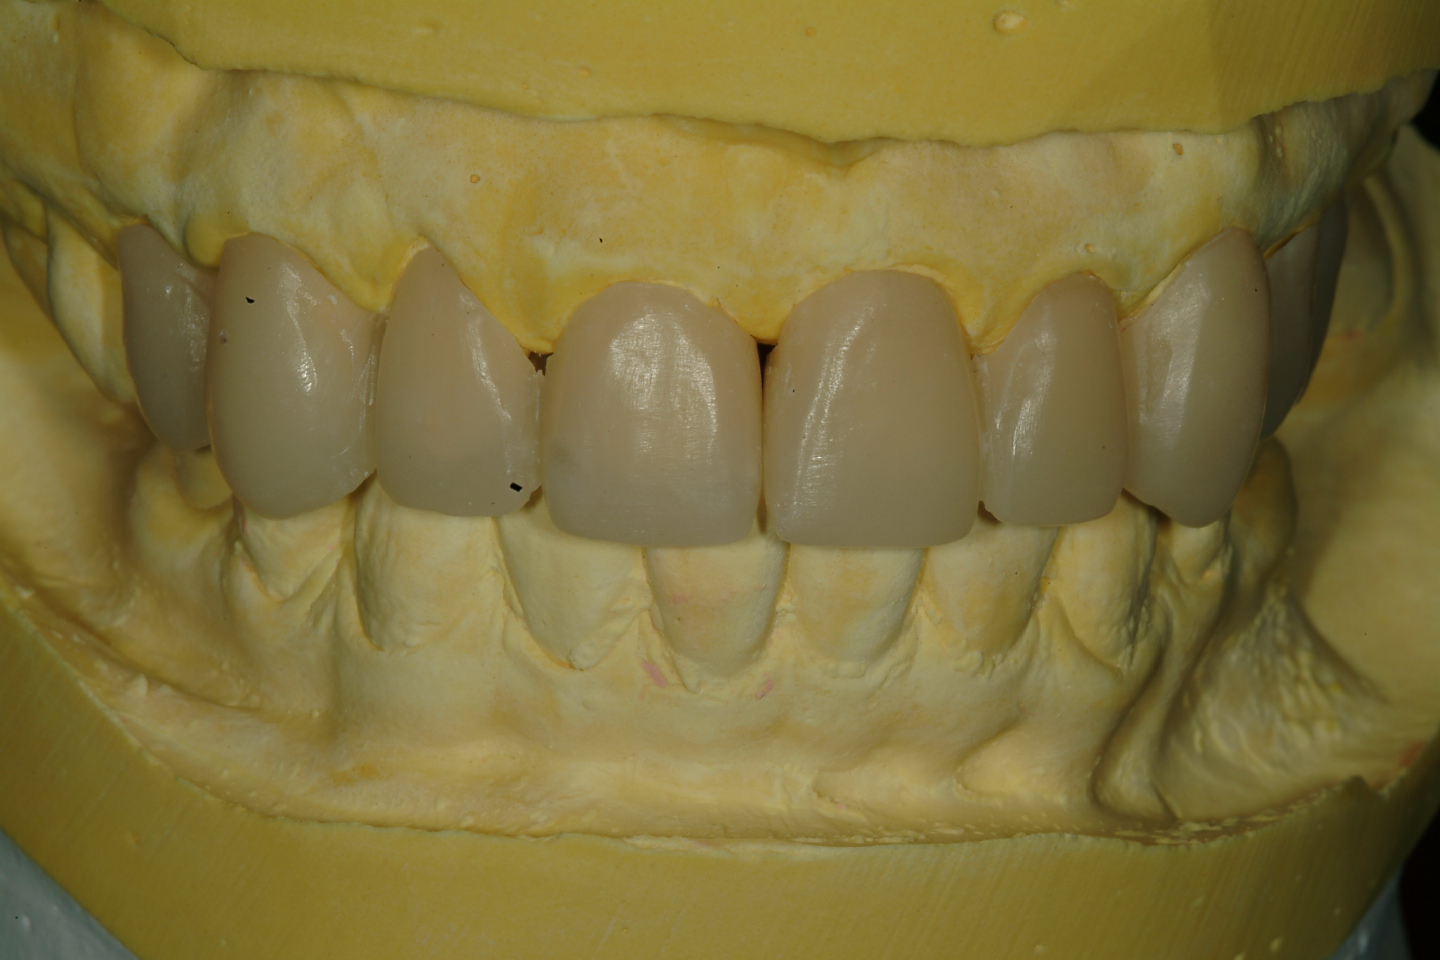

三、上咬合器後 , 與病患討論未來假牙外型(圖三)

圖三 |